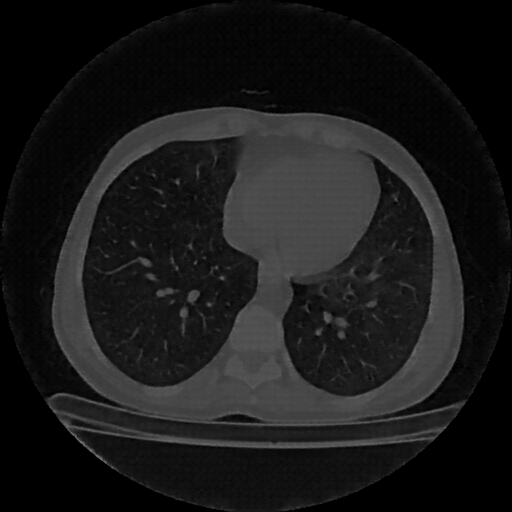

Reconstructed NATIVE CT scan (cycle consistency)

No window - Raw intensity values

Lung window (WL -600, WW 1500 β†’ Low βˆ’1350, High +150)

Mediastinum window (WL 40, WW 400 β†’ Low βˆ’160, High +240)